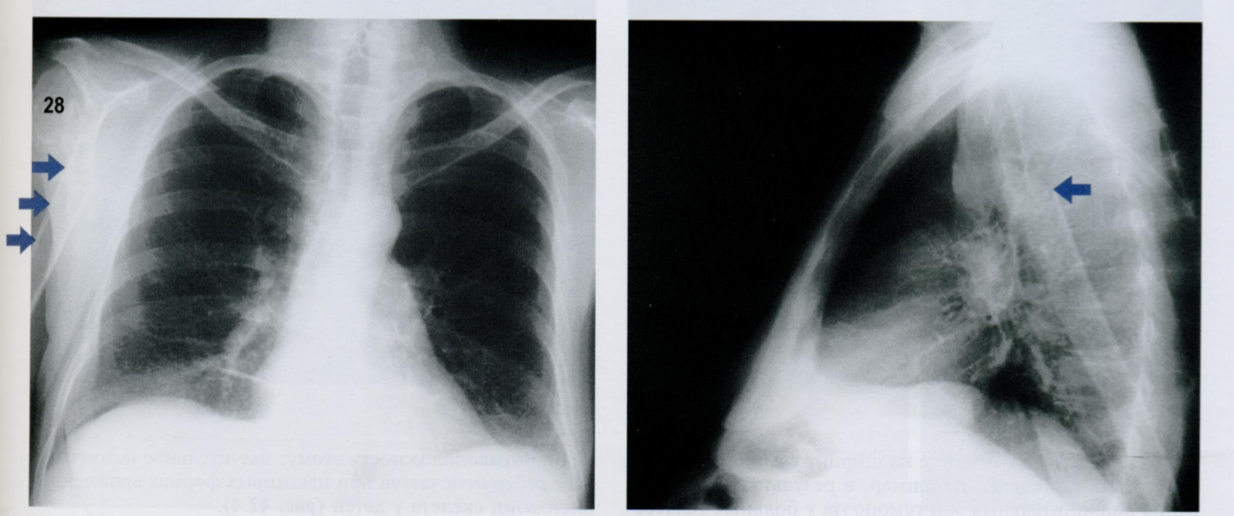

Обратите внимание на тень молочной железы (стрелочки), оцените симметричность теней слева и справа.

Пациентка после левосторонней мастэктомии с просветлением в нижних отделах с соотвествующей стороны (звездочка) в связи с отсутствием молочной железы (стрелочки).

Если есть сомнения, можно внимательнее рассмотреть подмышечную область на предмет возможного наличия металических клипс после иссечения ЛУ подмышечной впадины (фото ниже).

Ключевой момент - не ошибиться, принимая уменьшение прозрачности с одной стороны за выпот или внутрилегочное образование.